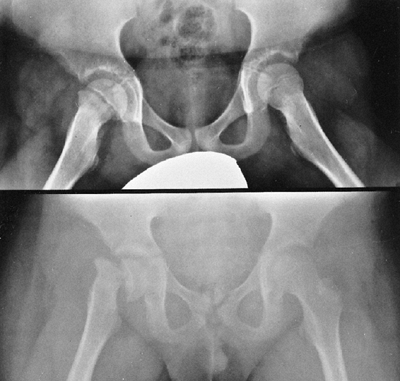

Radiographs of the pelvis usually show various degrees of coxa valga,

and in nearly 20% of patients there is radiographic evidence of

protrusio acetabuli (69,70).